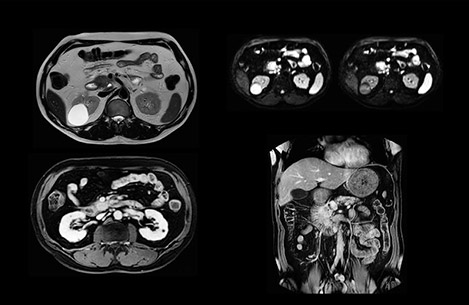

In this example the image quality of the MultiVane XD images is evidently better than in the images without MultiVane XD. Ingenia 1.5T with dS Torso coil solution.